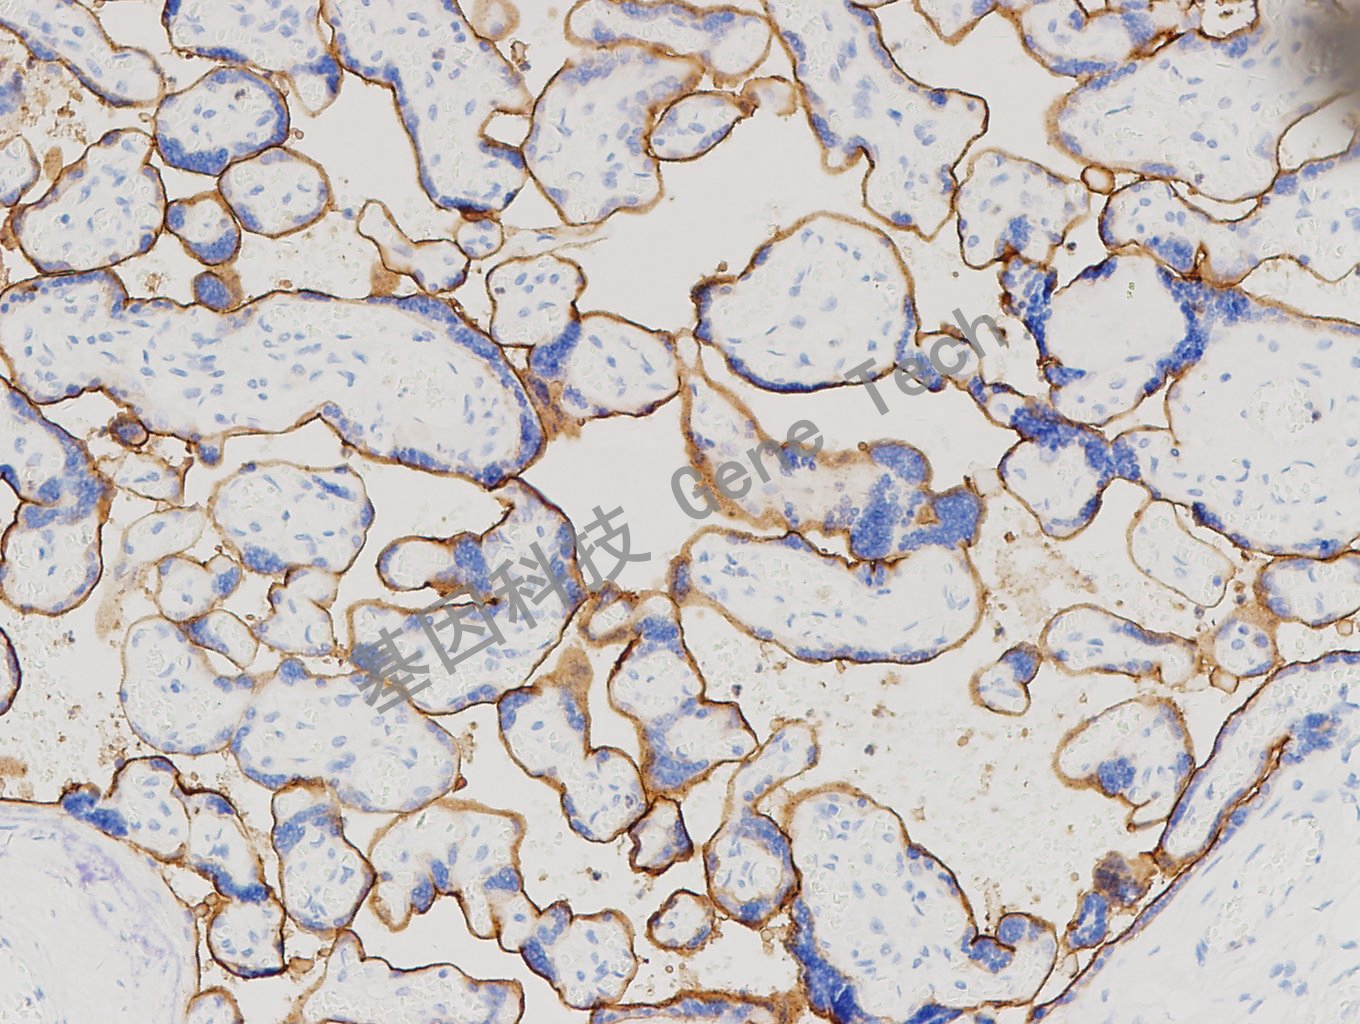

PD-L1 兔抗人 PD-L1 抗体试剂(免疫组织化学法)(GR110)

| 克隆号:GR110 | 种属:兔 | 适用染色系统:GTvisionTM |

| 预处理:高pH热修复 | 阳性部位:细胞膜 | 阳性对照:胎盘 |

| 简介:PD-L1(Programmed cell death ligand 1, 程序性细胞死亡配体1)是I型跨膜蛋白,参与细胞调节和免疫反应。广泛表达于活化T/B细胞、单核/巨噬细胞、树突状细胞、间质干细胞、胎盘滋养层细胞、血管内皮细胞、上皮细胞、成纤维网状细胞、胰岛细胞、心肌内皮和胸腺皮质上皮细胞等。在肺癌、尿路上皮癌、胃癌、宫颈癌、头颈癌、食管癌、乳腺癌、结直肠癌、黑色素瘤、卵巢癌、肾细胞癌、胰腺癌等肿瘤中阳性表达,与肿瘤的免疫逃逸机制相关。 | ||

| 胎盘石蜡切片,用 PD-L1(GT2562)染色,细胞膜阳性,DAB 显色。 | ||